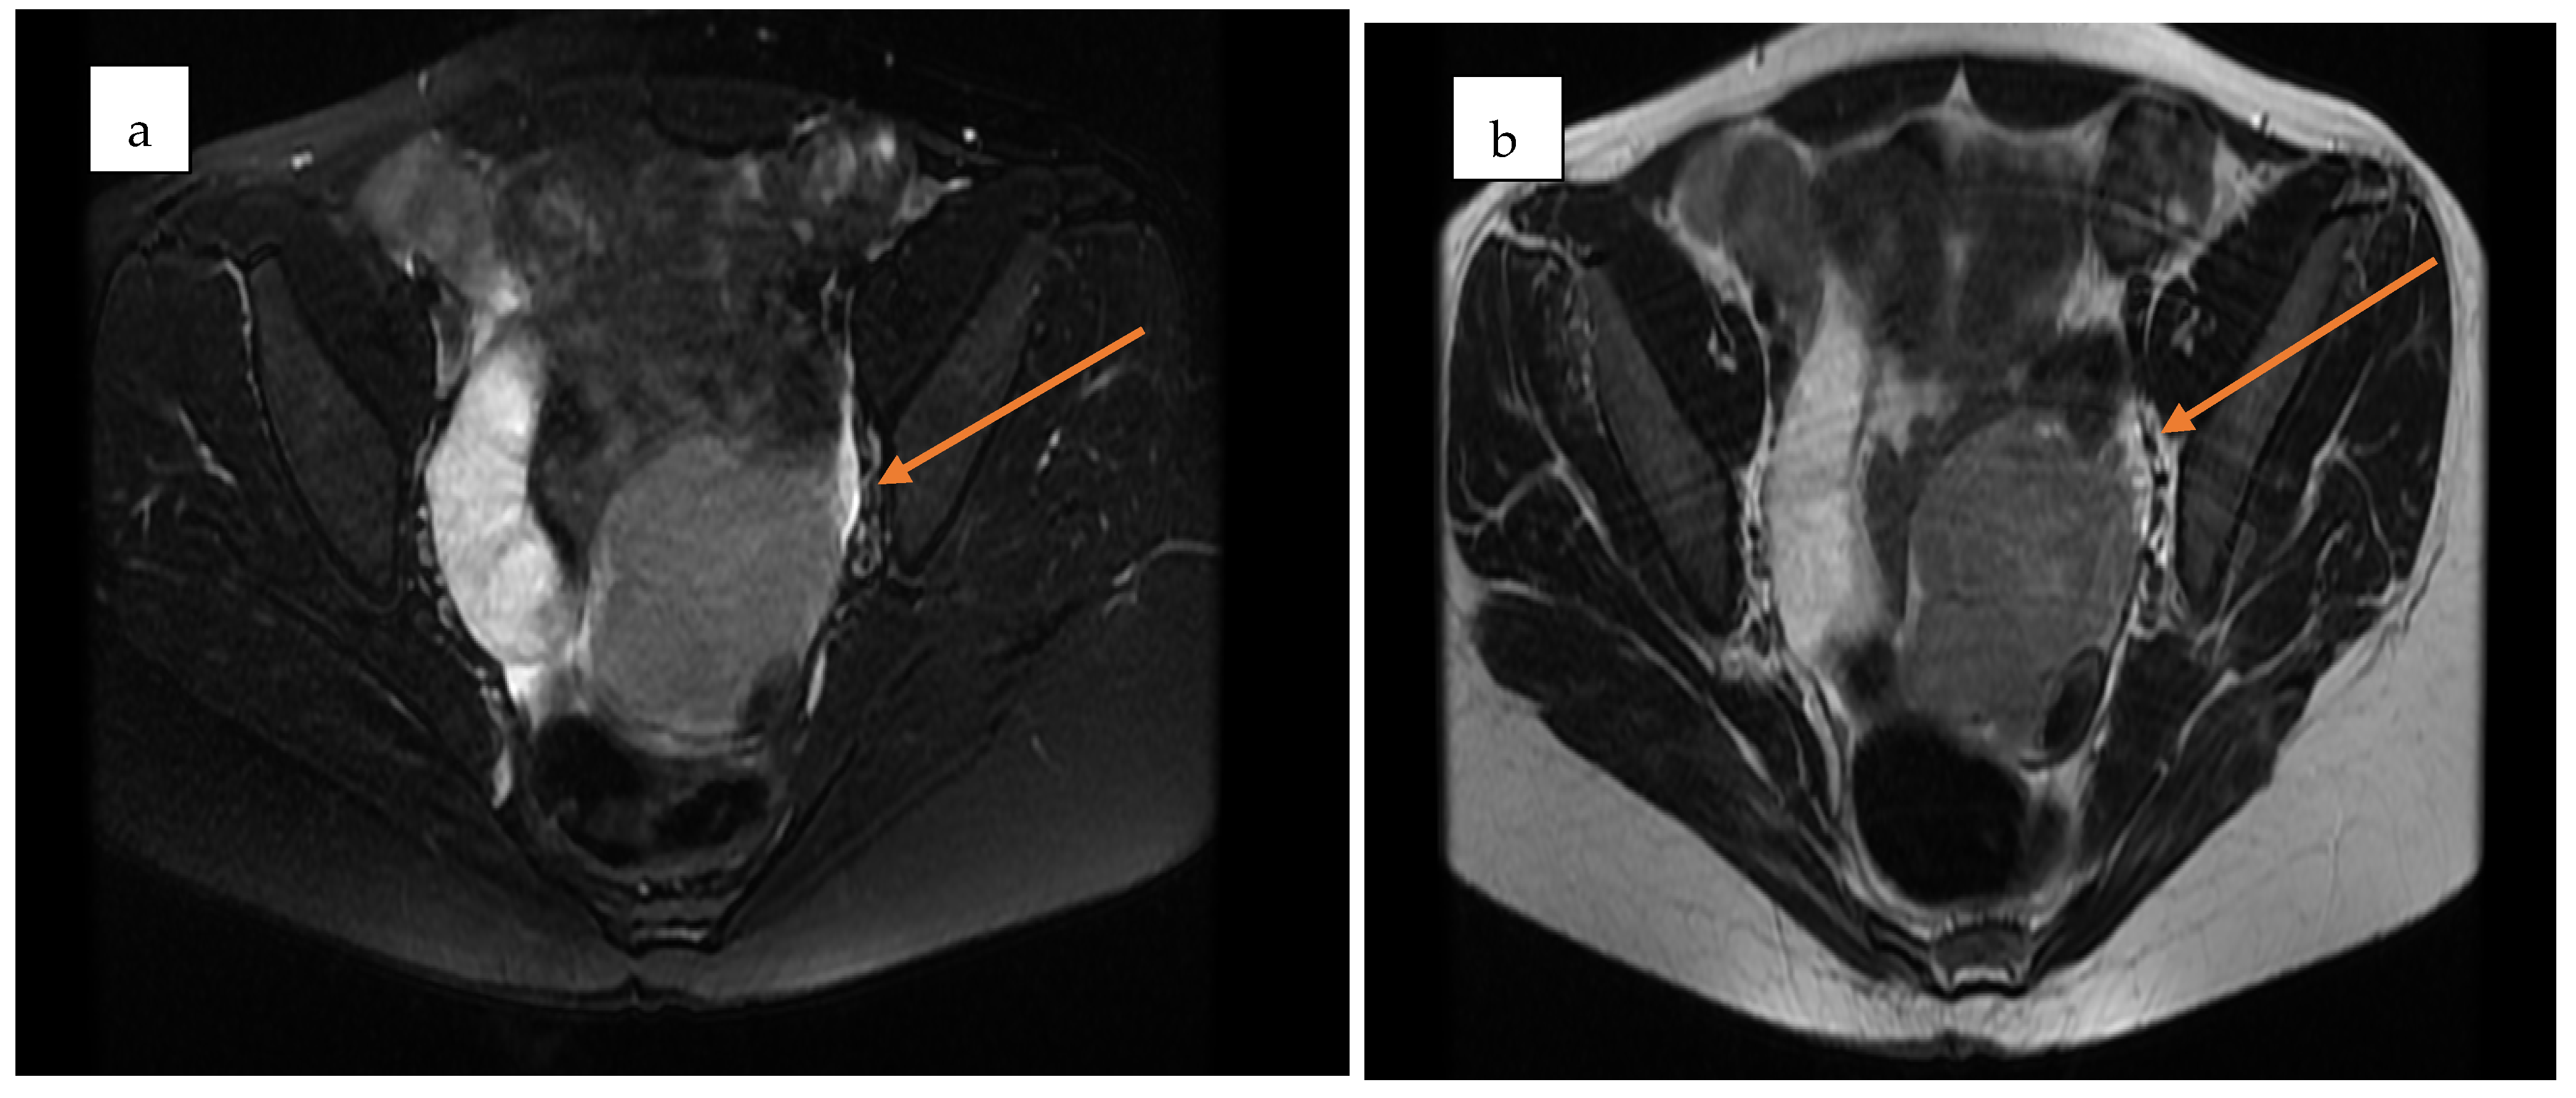

Pelvic MRI demonstrated a well-circumscribed, encapsulated, septated round-oval mass (62 × 74 mm) situated in the pouch of Douglas, adjacent to the left adnexa. The lesion contained multiple small cystic areas and a nodular component with low signal intensity on T2- and T2FS-weighted sequences and high signal intensity on T1, findings consistent with intratumoral hemorrhage (Figure 2 and Figure 3). After contrast administration, the solid component of the mass showed vascular enhancement.

Figure 3. Axial pelvic MRI of the adnexal mass in the pouch of Douglas. (a) Pre-contrast T2-weighted image showing a well-encapsulated, septated mass with mixed cystic–solid components (yellow arrow). (b) Post-contrast image demonstrating enhancement of the solid nodular component, consistent with vascularization (yellow arrow).